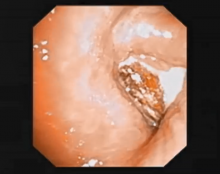

Flexible Bronchoscopy Mediated Foreign Body Removal From Right Lower Lobe Bronchus Using a Cryoprobe [1]

Impaction of a foreign body in the bronchus is common. Flexible bronchoscopy with use of a cryoprobe can be conveniently used to remove an impacted foreign body in the bronchus. This video demonstrates this process. Sometimes the diagnosis can be missed. Surgeons should have a suspicion of a foreign body whenever there are atelectatic changes and consolidation on radiographic imaging.